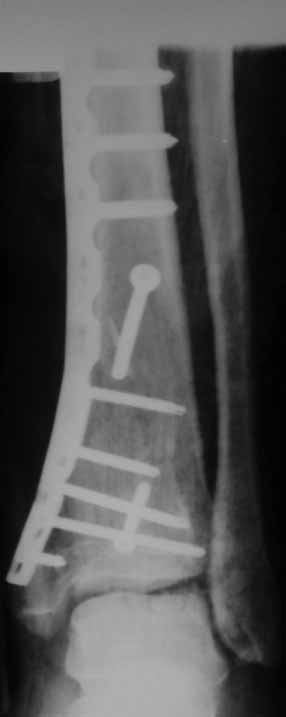

Извиняюсь пропал - оперировал "пилон". В форуме не хотел обсуждать финансовые возможности пациента. Потянул комбинированную пластину. Опыт общение с пластиной "крест" есть - не очень понравилось - слишком много места занимает, даже с учетом обрезаний лишнего. Сделал доступ огибающий медиальную лодыжку спереди. В переднем крае оказался достаточно крупный отломок - удалось зафиксировать винтом. Дефекта кости не оказалось.